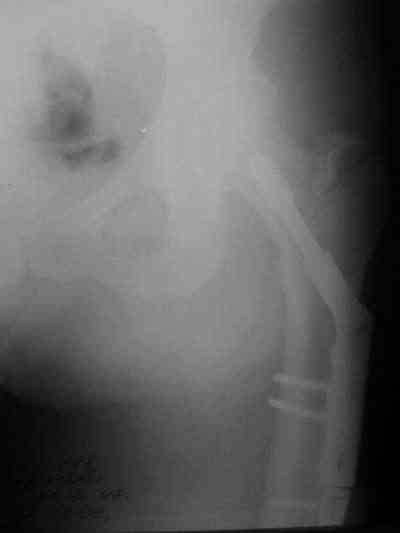

Около 10 дней назад выполнил остеосинтез бедренной кости LC-DCP и DHS по поводу фрагментарного оскольчатого перелома в средней трети и чрезвертельного перелома.

Снимки в приложении.

В приложении и имеющийся в наличии брейс. Приношу извинения за низкое качество снимков.

Брейс тут конечно не поможет!

Глубокоуважаемый Никита!На бедре стоило бы обязательно провести межфрагментарный стягивающий винт и предварительно надо бы слегка изогнуть пластину,ну и может быть трансплантат по внутренней поверхности.А параллельно большому винту DHS провести спонгиозный винт для ротационной стабильности.Так,что с нагрузкой не нада тараписся!

Уважаемый Никита, очень меня расстроило не качество снимков, а сам остеосинтез. Вертельный перелом, пожалуй, еще срастется. А диафиз может преподнести ожидаемое, предуготованное осложнение: несращение и перелом импланта, даже если это суперфмрменная пластина.:(